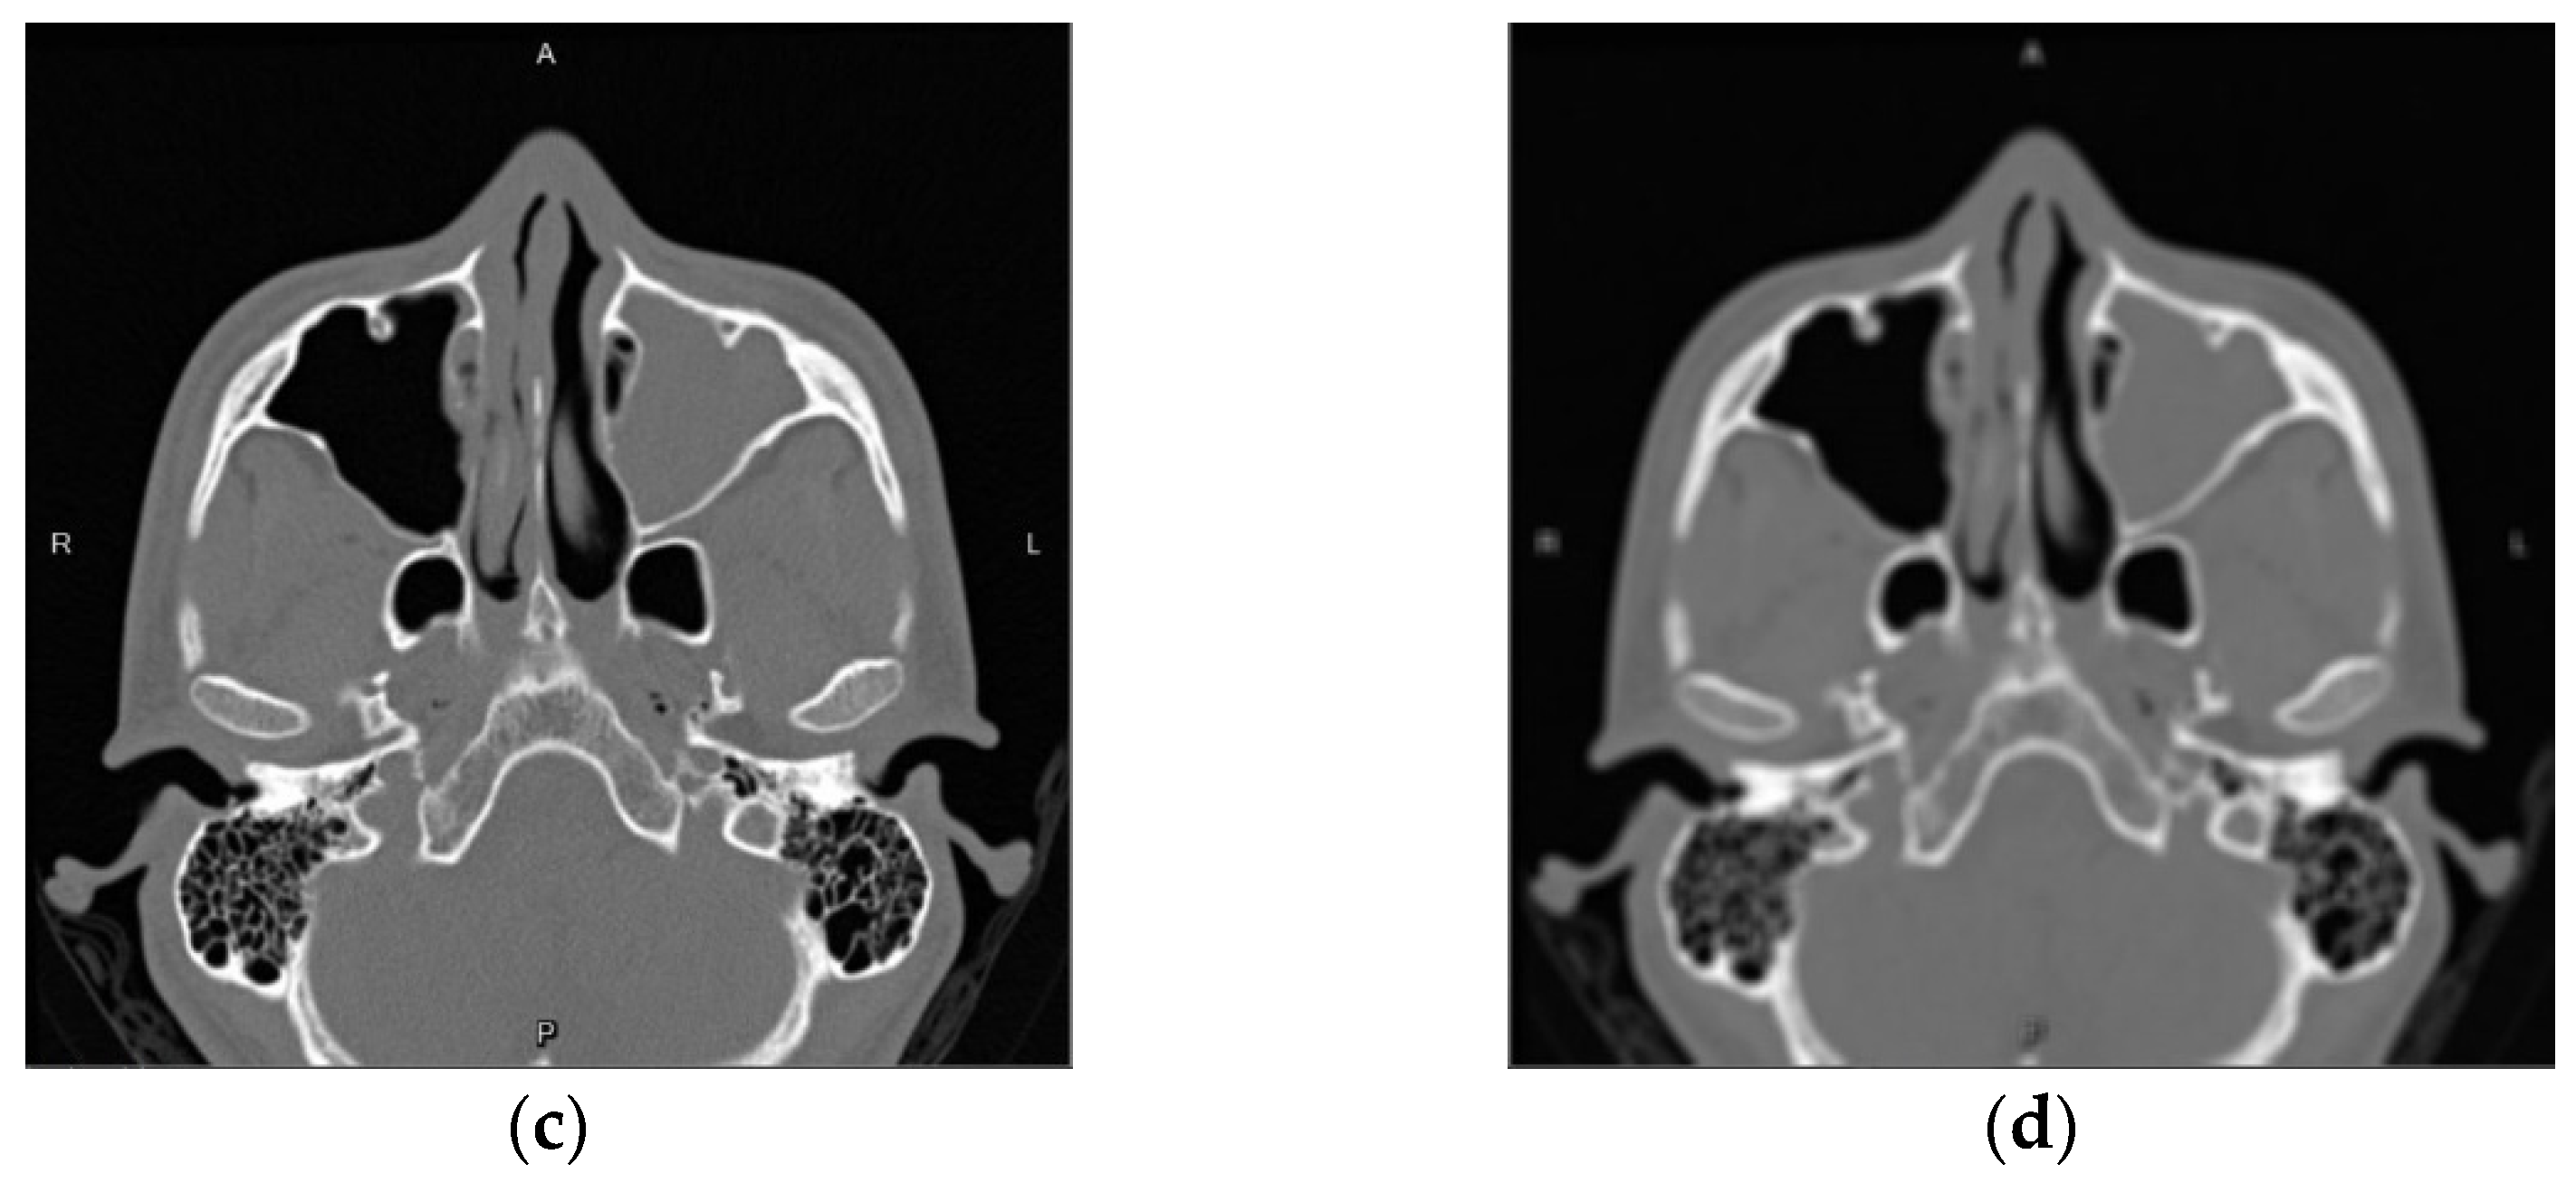

3.1.2. Gaussian Noise

3.1.3. Mixup